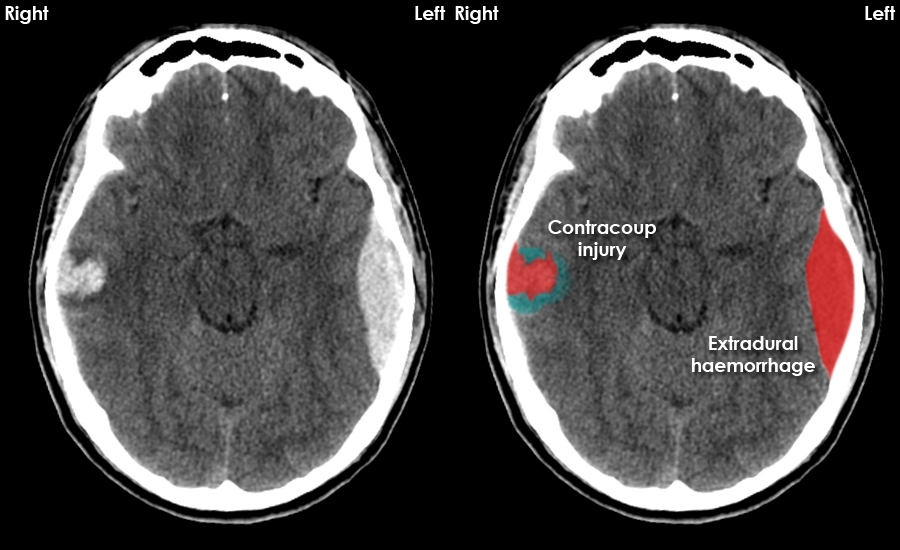

From www.radiologymasterclass.co.uk

CT brain image gallery EDH Is Ct Head Same As Ct Brain This procedure is noninvasive, meaning it doesn’t require. Computed tomography (ct) scans of the head are an important diagnostic tool in modern medicine, offering detailed images of. A cranial ct scan is known by a variety of names as well, including brain scan, head scan, skull scan, and sinus scan. Magnetic resonance imaging (mri) of the head provides superior information. Is Ct Head Same As Ct Brain.